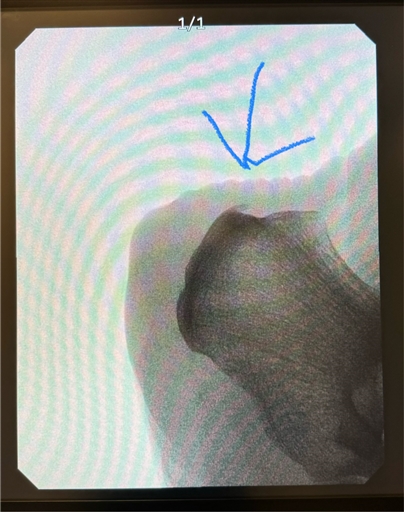

Bild uppladdad av Joakim

Hejsan! Här igen…… :)

Var till en fotläkare som konstaterade inflamation i fästet på hälsenan, känns som att jag har ett blåmärke på hälen mot hälkappen. Fick en veckas kur av NSAID (Etoricoxib 90mg) och info om att det bara är att köra på så länge smärtan inte stegras under aktivitet eller är kvar efter 24h. Han gjorde även en snabbröntgen och jag har en lite utväxt på just den hälen och det är tydligen den som gör ont. Han sa att det inte är någon fara utan det bara är så och att allt läker av sig själv.

Ni med erfarenhet av liknande skador, hur lång tid tog det? Vad var bäst? Hur kan man snabba på läkning? Saker att undvika etc?